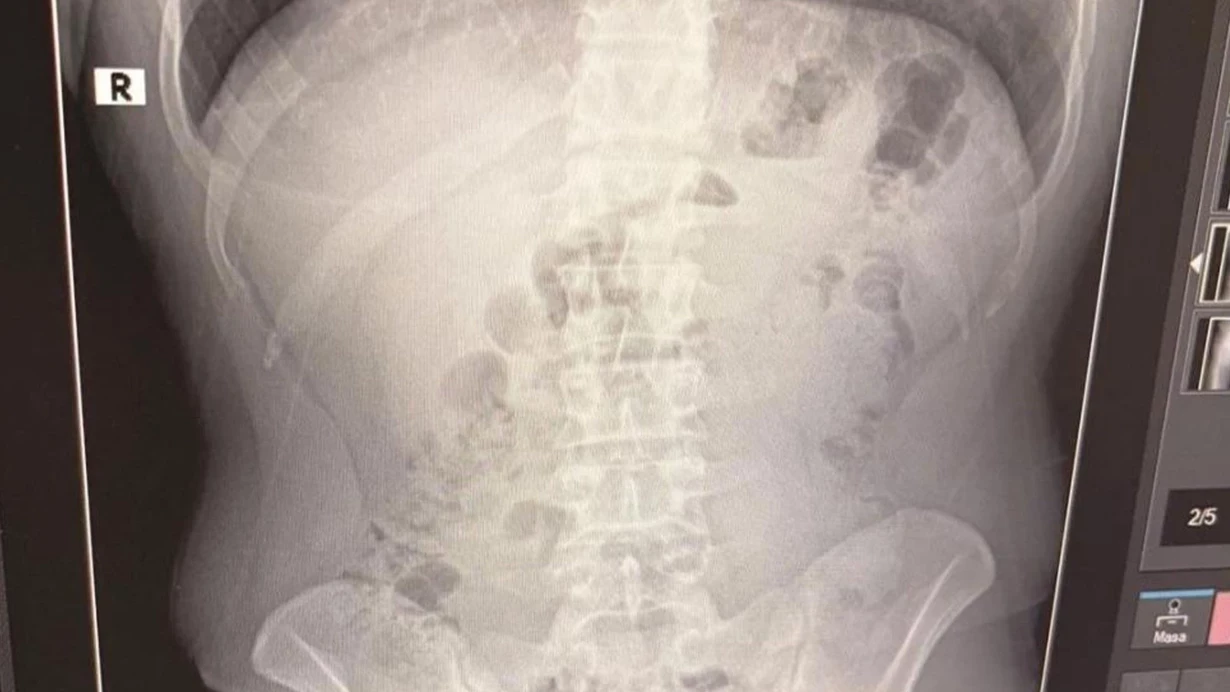

Uşakda narkotik ticarəti ilə məşğul olduqları iddia edilən 3 İran vətəndaşının evində və mədəsində 1 kilo 516 qram metamfetamin ələ keçirilib.

Manset.az Türkiyə mediasına istinadən xəbər verir ki, Uşak İl Təhlükəsizlik Müdirliyi Narkotiklə Mübarizə Şöbəsi qrupları narkotiklərin İrandan Türkiyəyə gətirildiyinə dair kəşfiyyat məlumatının ardından araşdırma başlatdı . Texniki və fiziki müşahidədən sonra İrandan İzmir Adnan Menderes Hava Limanına gələn və daha sonra taksi ilə Uşaka gedən YT, AT və MJ Kurtuluş məhəlləsindəki bir ünvanda yaxalanıb.